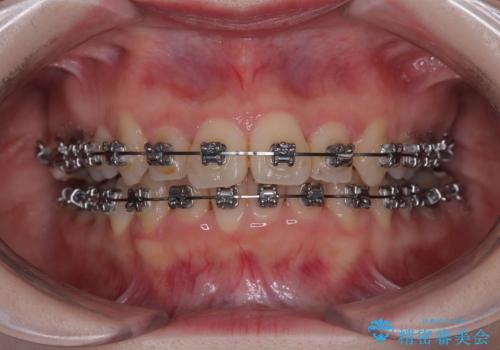

- メタルブラケット

- 1年11ヶ月

- 上下前歯のデコボコを気にして来院された患者様です。

マウスピースでもワイヤー装置でも対応可能でしたが、右側の咬み合わせが上顎がやや前方に位置していることから、補助装置を使用することが推奨されました。

自己管理の煩わしさを気にして、補助装置併用によるワイヤー装置での矯正治療を行うこととしました。

右上と左下の第一大臼歯2本が周辺の歯と比べて位置がずれていたため、ゴムかけやワイヤーに曲げを入れることで移動を試みましたが、どうよら癒着をしており、移動困難と判断されました。

見た目や咬み合わせに違和感がないとのことで、癒着歯の無理な移動は試みずに治療を終えることとしました。